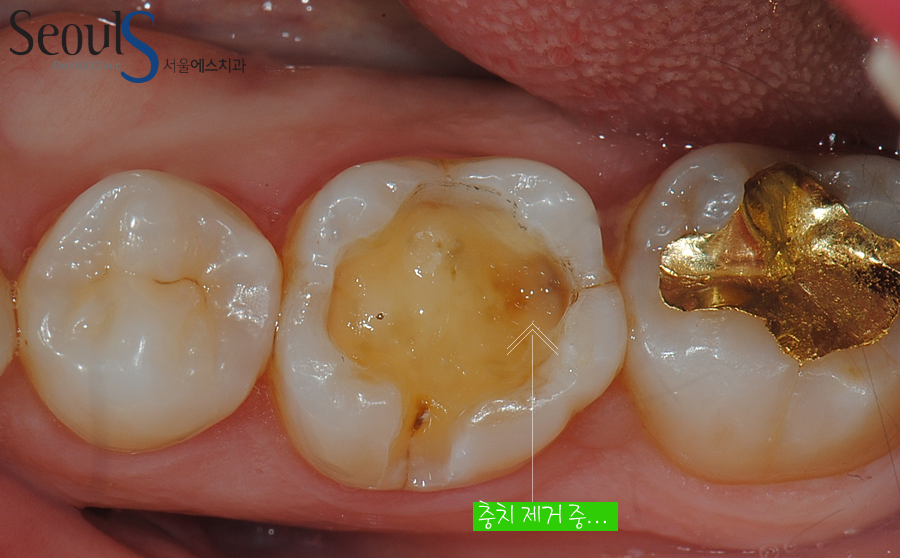

치아 속 충치를 제거하고 있습니다

충치 제거 후 빈 공간을 다시 CAD/CAM 인레이로 때워 치료를 마칠 예정입니다